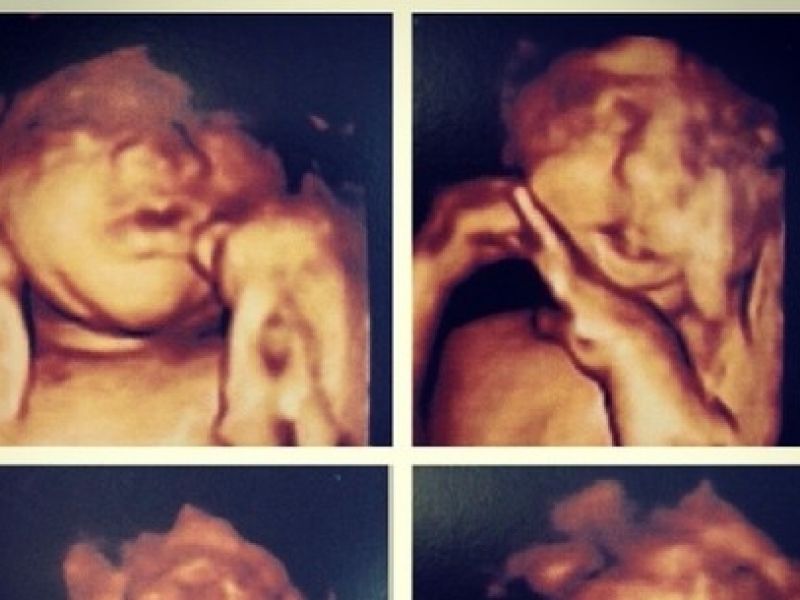

19 de novembro de 2013 Jaque Khury mostra rosto do filho no ultrassom: “Não vejo a hora de ele nascer”